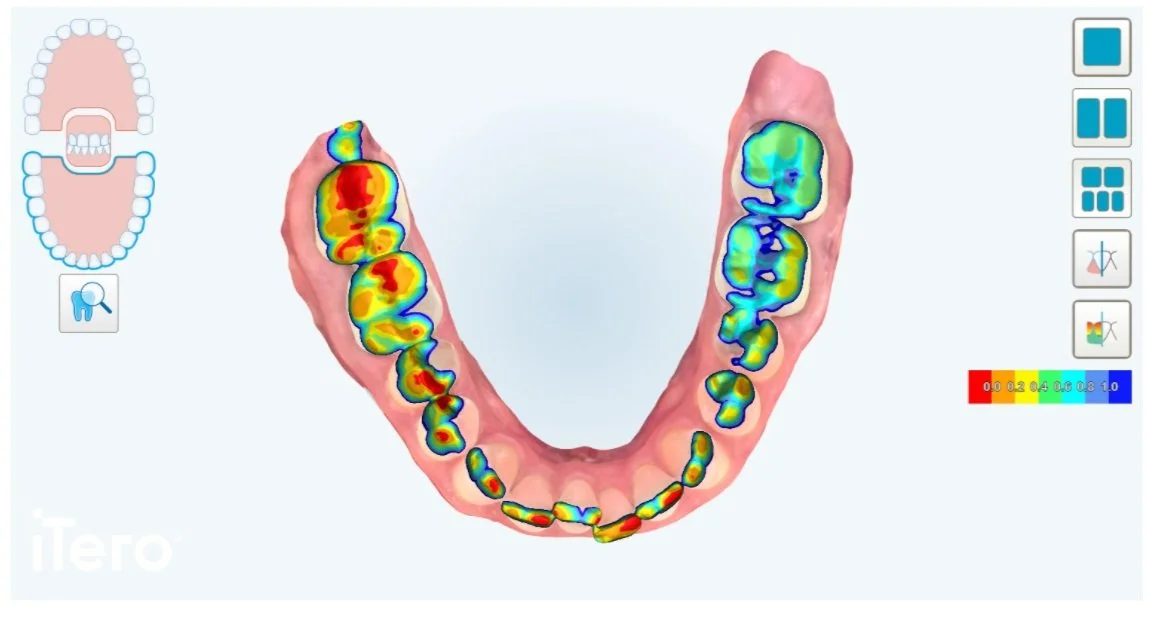

4. It provides an occlusogram for bite analysis

This advanced technology, using its rainbow-colored occlusal clearance legend, allows us to thoroughly analyze the overall structure and function of your bite.

This allows us to detect signs of occlusal trauma including chipping, wearing, thinning, recession and abfraction lesions. Through this feature, we are able to proactively provide solutions for things you cannot see but may eventually feel – saving you time and money in the future.